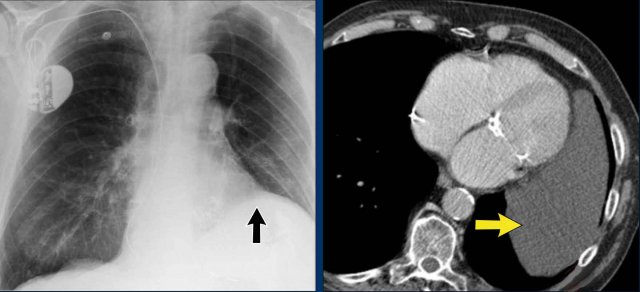

Pericardial effusion

When encountering an enlarged cardiac silhouette on chest radiography, it is essential to consider pericardial effusion as a potential mimic of cardiomegaly.

Case Example 1: Pericardial Effusion Mimicking Cardiomegaly

• On the chest radiograph, the patient appears to have a dilated heart.

• However, CT imaging clearly demonstrates that the apparent enlargement is due to significant pericardial fluid accumulation, not true myocardial chamber enlargement.

Postoperative Pericardial Hemorrhage

In patients with recent cardiac surgery, a sudden change in heart size on chest X-ray should raise suspicion for pericardial bleeding, which may be life-threatening.

Case Example 2:

• A postoperative patient showed a change in the cardiac silhouette.

• Echocardiography detected only a minimal pericardial effusion.

Case Example 2 - CT imaging

• CT imaging revealed a large posterior pericardial effusion compressing the left ventricle (blue arrow: effusion; red arrow: compressed, contrast-filled left ventricle).

• Surgical exploration confirmed a large posterior pericardial hematoma.

Note

: Minimal anterior fluid on ultrasound may underestimate the true volume if the effusion is loculated posteriorly, highlighting the value of CT in postoperative cases.